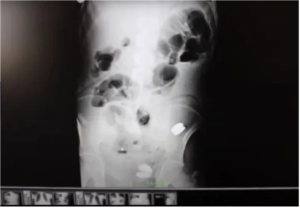

أصيب الأطباء، بصدمة كبيرة بعد العثور على أكثر من 200 عملة معدنية ومسامير وبطاريات وشظايا زجاج داخل معدة رجل في تركيا، بحسب ما جاء في صحيفة مترو البريطانية.

ونقل برهان ديمير من إبيكيولو في تركيا، شقيقه الأصغر إلى المستشفى بعد أن اشتكى من آلام في البطن

ولكن عندما أجرى الأطباء كشفًا داخليًا باستخدام الموجات فوق الصوتية والأشعة السينية،

اندهشوا من اكتشاف 233 عنصرًا في معدة البالغ من العمر 35 عامًا.

وشملت هذه العملات٠٠

عملات ليرة واحدة وبطاريات ومغناطيس ومسامير وقطع زجاج وأحجار